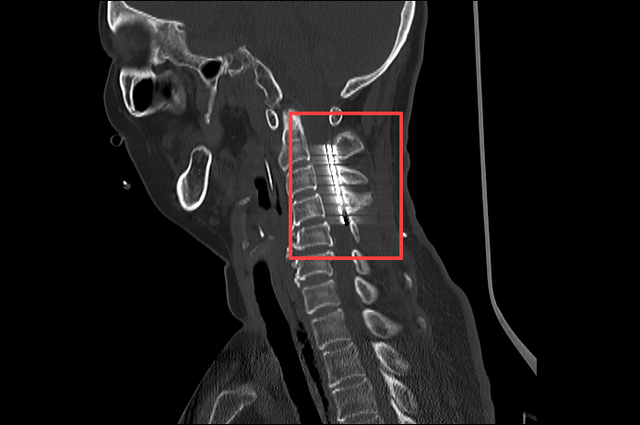

▲术后CT:电极植入位置精准

一个月后,在王文华主任的指导下陈龙主任医师与陆维主治医师为张女士在全麻下行SCS永久植入术。